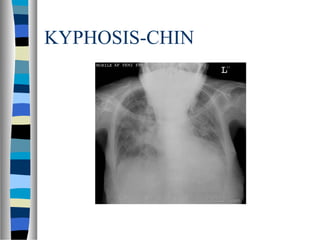

KYPHOSIS-CHIN